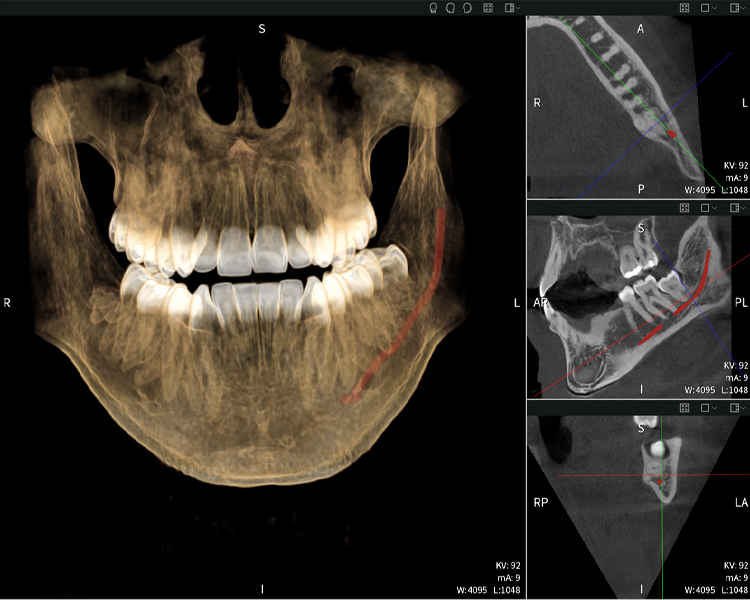

Figura d: Resultados de imagen de Seethrough Max, sobre un fondo negro.

Figura d

Las figuras b–d muestran varias vistas de una reconstrucción 3D de la mandíbula, proporcionando una visión general completa de la anatomía mandibular, la posición de los nervios en relación con los dientes y permitiendo evaluar la simetría y alineación dentaria.

La figura d muestra el diente 48 previamente tratado, con la corona retirada y las raíces dejadas en proximidad al nervio, lo que ilustra el alto riesgo de daño nervioso.